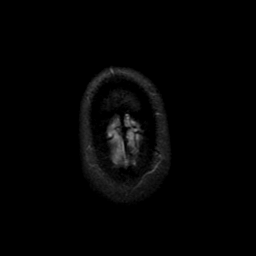

MR Study #9, April 14, 1991 -- Slice #48

[Home][Help][Clinical][Tour 1][Tour 2] Slice 48